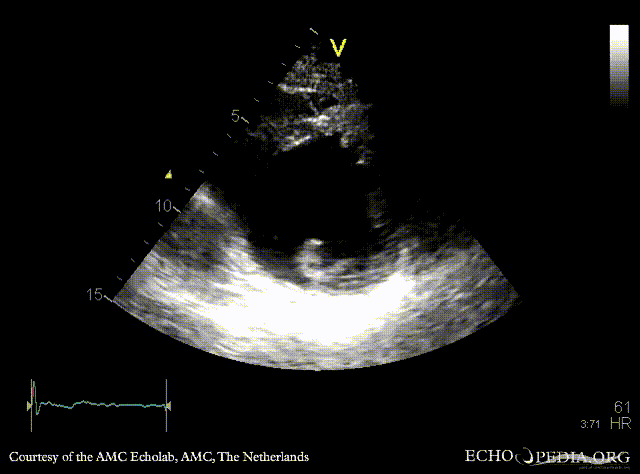

Infarction of posterior and inferior wall

Courtesy of: AMC Echolab, AMC, The Netherlands

E00526.gif E00527.gif

A4CH: akinesia of inferoseptal wall A2CH: akinesia of inferior wall